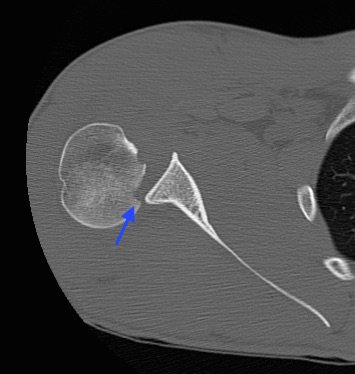

Radiographs demonstrated posterior displacement of the humeral head on the “Y” view (see white arrow) and widening of the glenohumeral joint space on anterior-posterior view (see red arrow). The findings were consistent with posterior dislocation and a Hill-Sachs type deformity.  Sedation was performed and reduction was attempted using external rotation, traction counter-traction. An immediate “pop” was felt during the procedure. Post-procedure radiographs revealed a persistent posterior subluxation with interlocking at posterior glenoid. CT revealed posterior dislocation with acute depressed impaction deformity medial to the biceps groove with the humeral head perched on the posterior glenoid, interlocked at reverse Hill-Sachs deformity (see blue arrow).